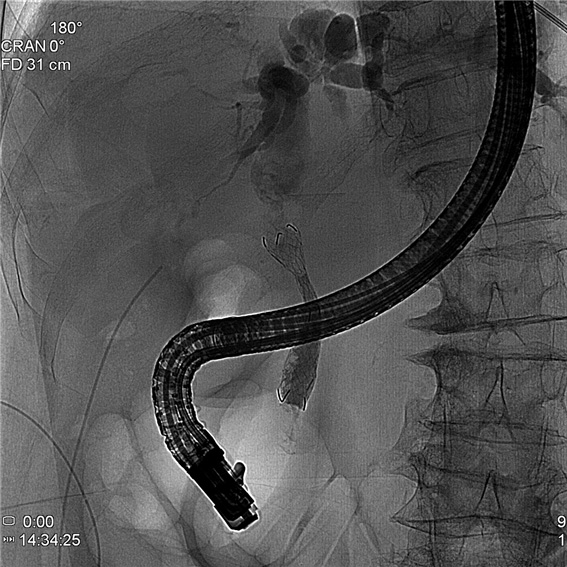

증례 1. 복통으로 내원하여 담도 결석에 의한 담도염 진단 환자에서 담도내시경을 이용한 담도 결석 제거술 시행 1예